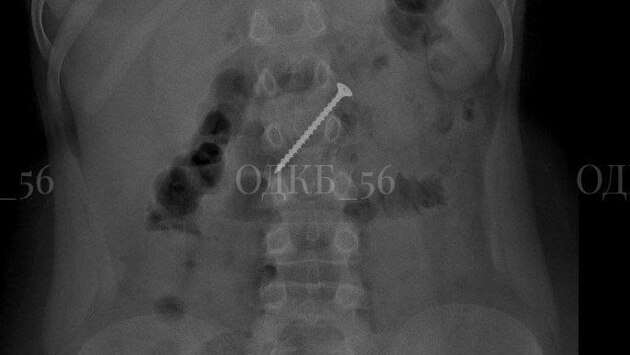

Проглотил пятисантиметровый саморез: оренбургские врачи спасли ребенка

Специалисты Областной детской клинической больницы вытащили из кишечника ребенка саморез. Своевременное вмешательство профессионалов спасло юному пациенту жизнь.

Девятилетний мальчик попал в больницу после того, как родители заметили тревожные симптомы. После обследования врачи обнаружили инородное тело в желудке ребёнка.

Специалисты оперативно провели операцию под общим наркозом и извлекли опасный предмет из кишечника пациента, избежав серьезных последствий, включая риск непроходимости и прободения стенки органа.